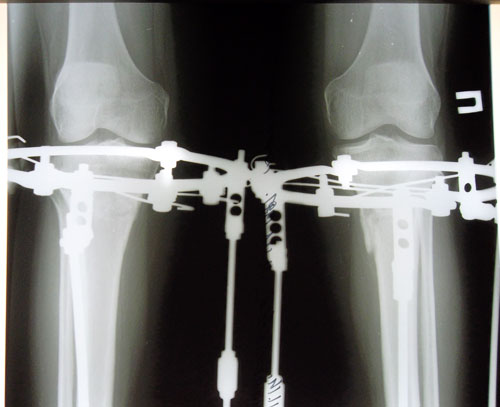

Дата операции 16.06.2014г.

Дата снятия аппаратов 04.11.2014г.

Срок лечения 138 дней.

рентген в день снятия аппаратов.